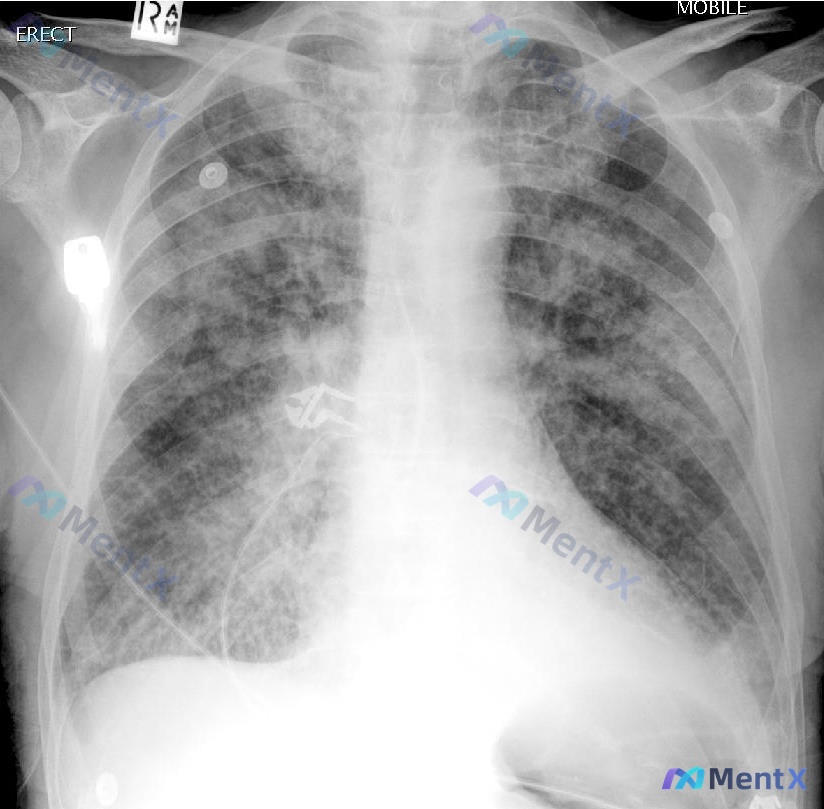

纳洛酮促醒后突发双肺弥漫浸润,最可能的病因是什么?

整理到一个急诊病例,第一眼思路其实挺容易分叉的,放出来大家讨论看看。 基本情况:55岁男性,有多种药物滥用史,40包年吸烟史,2年前确诊可卡因心肌病+心梗。 本次起病:在家中被发现严重昏迷,EMS到场时SpO2只有40%,予纳洛酮后立刻清醒,SpO2升至90%;但随后发现患者呼吸做功明显增加,肺部有...